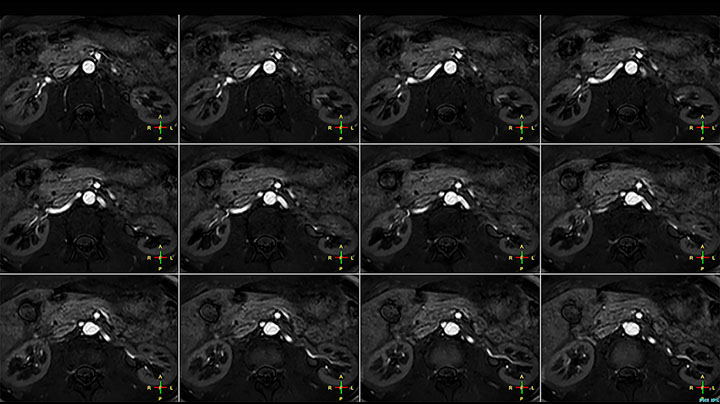

MRI of Pancoast tumor

Although the area between the neck and the top of the lung is one of the most difficult areas for MRI, Prodiva 1.5T images show good quality in this 56-year-old male with Pancoast tumor on the right. mDIXON TFE images shows excellent fat suppression in the neck area and the DWI shows almost no distortion.

Prodiva MRI pancoast tumor DWI, Seirei Mikatahara

Prodiva MRI pancoast tumor mDixon, Seirei Mikatahara

Prodiva MRI pancoast tumor dynamic, Seirei Mikatahara